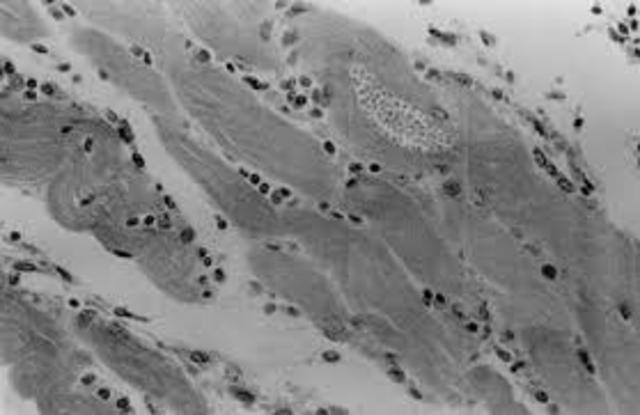

describió formas tisulares de T. cruzi y lesiones en el corazón (Chagas crónico)